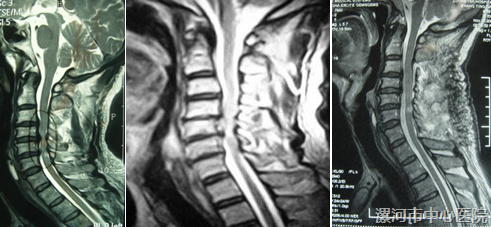

脊髓型颈椎病(CSM),是临床常见的疾病,颈椎管扩大成型术(单开门等)是治疗 CSM 最常用的术式。

目前最常采用的术式:颈3-7椎管扩大成型术,但术后患者出现颈肩部疼痛、颈椎后凸畸形 顽固性轴性症状、等并发症,发生率高达45%~80%,对术后康复造成巨大影响。

颈后伸肌群在维持颈椎生理曲度、稳定性方面起重要作用,其中颈半棘肌(SSC) 最为重要,术后颈椎前凸的丢失、轴性疼痛 与 损伤SSC 有关。

解剖学上:SSC是附着在颈椎2、3~颈7、胸1棘突上的一串肌腱和肌肉纤维,其中颈2、3和颈7胸1两端的止点最为重要,如弓箭两端的皮筋,维持颈椎前曲,传统的颈3—7颈椎管扩大成型术,切断了颈2/3棘突上的肌肉,为较为完整的保留SSC。